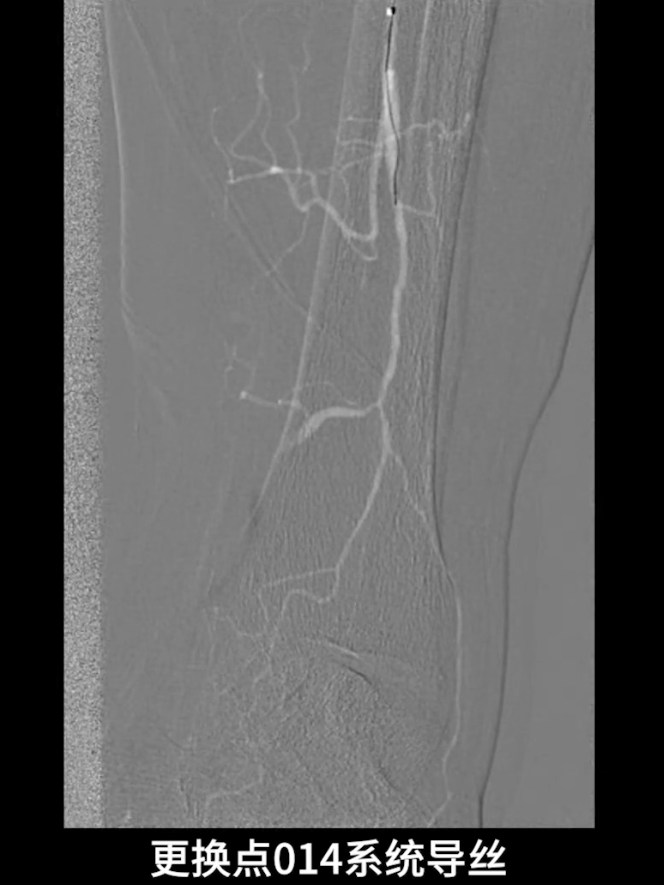

流出道扩张与优化:使用3.0×200mm PTA球囊对“胫腓干-腓动脉”全程进行扩张;

更换0.014系统导丝,经交通支选入胫后动脉远端,

再以2.0×40mm球囊扩张残余狭窄,并压迫远端逆行穿刺点止血,确保膝下流出道通畅。